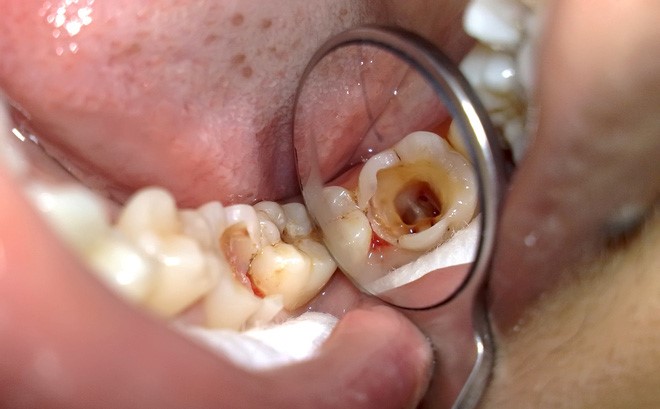

Viêm tủy răng là tình trạng vùng tủy bị vi khuẩn tấn công gây sưng viêm kèm theo các cơn đau nhức dữ dội. Có nhiều nguyên nhân dẫn đến bệnh lý này như: sâu răng lâu ngày không điều trị, mòn men răng hoặc răng bị nứt, mẻ, vỡ mạnh do tai nạn gây ra.

(Viêm tủy răng là bệnh lý phổ biến)(**)